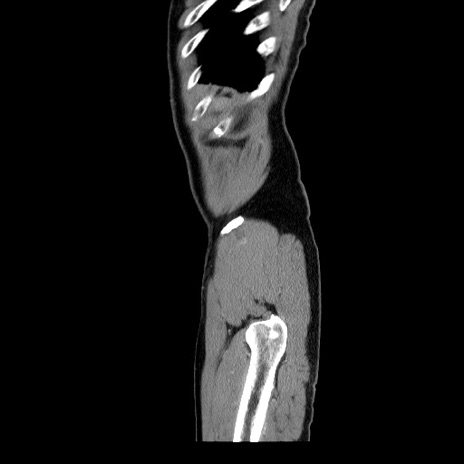

症例34(矢状断像)

【症例】60歳代 男性

【主訴】右鼠径部膨隆

【現病歴】1年程前より右鼠径部膨隆あり。自己にて還納可能だったため放置していた。3時間前より右鼠径部の脱出を認め、還納困難となり受診。

【身体所見】右鼠径部に小児頭大の膨隆あり。弾性硬であり、用手還納は困難。左鼠径部にも膨隆を認める。脱出はなし。